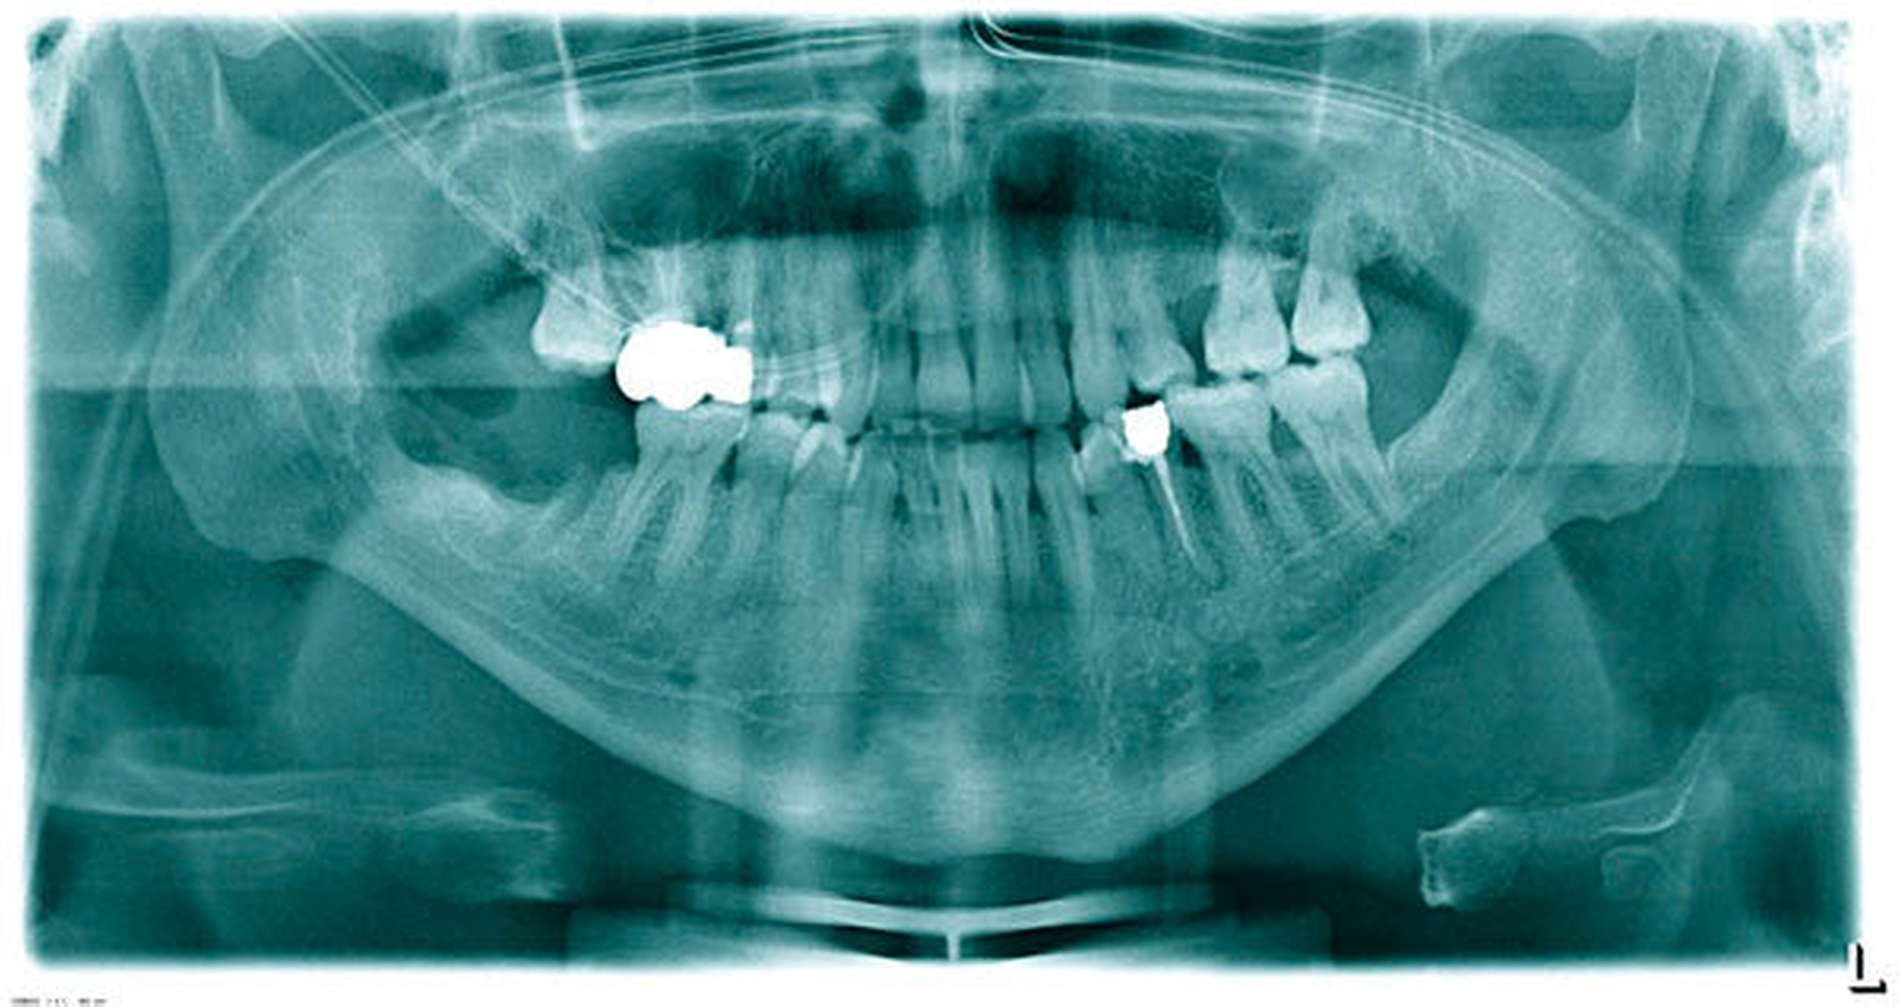

Nach Aufklärung des Patienten umfasste die Therapie der Wahl die In-toto-Resektion des Befunds zusammen mit der Extraktion der Zähne 47 und 48. In Intubationsnarkose erfolgte eine mesiale Schnittführung an 47/48 mit Entlastungen im Bereich des aufsteigenden Astes und nach vestibulär. Zu sehen war eine derbe, weißliche und adhärent mit 48 verwachsene Läsion (Abbildung 3), die gemeinsam mit dem Zahn entfernt wurde (Abbildungen 4 und 5). Der Zahn 47 wurde ebenfalls extrahiert und nach Kürettage und Glättung der Knochenkanten ein Kollagenflies in den Defekt eingelegt. Die anschließende plastische Deckung erfolgte mehrschichtig (Abbildung 6).

Bei einem komplikationslosen postoperativen Heilungsverlauf konnte der Patient nach zweitägiger stationärer Überwachung in die ambulante Nachsorge entlassen werden.

Die histologische Aufarbeitung des etwa 3 cm x 2,5 cm x 2 cm großen Resektats ergab ein spindelzelliges Proliferat mit myxoidem Stroma (Abbildung 7) und Arrosionen des ortsständigen Knochens. Zur weiteren histogenetischen Typisierung wurde ergänzend eine immunhistochemische Untersuchung durchgeführt, die die Diagnose des odontogenen Myxofibroms bestätigte. Bei einem Nachsorgeintervall von insgesamt sechs Jahren zeigte sich sowohl klinisch als auch radiologisch kein Anhalt auf ein Rezidiv.